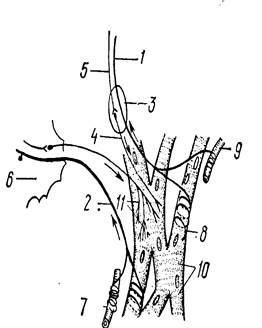

Ramurile de capăt ale dendritelor formate în miocardul numeroase terminațiile nervoase senzoriale care pot fi împărțite în două grupuri (Figura 2).

Fig. 2. Schema de inervarea inimii

1 - fibre vagale aferente; 2 - fibră aferente trece printr-un nod; 3 - intracardiac nod parasimpatic; 4 - fibre postganglionare; 5 - fibre preganglionari; b - ganglion simpatic stelat; 7 - mechanoreceptors; 8 - receptorii musculare; 9 - un vas de sânge; 10 - myocardiocytes; terminațiilor nervoase motorii - 11.

Un grup - mecanoreceptorii situate în țesutul conjunctiv din jurul arteriolelor și straturile intermediare. Ele apar atunci când o semnal în lumenul vaselor de sânge și tensiunea țesutului conjunctiv. impulsuri de la acești receptori aferenti provoacă o accelerare reflex a ritmului cardiac. Un alt grup - receptori musculare având forma unei spirale. Ele sunt specializate pentru a semnala contracția celulei musculare. În plus, cu participarea celulelor nervoase diferite sunt concentrate în ganglionul intracardiac format arc reflex local.